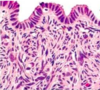

מהם המאפיינים ההיסטולוגיים של שחלות?

ovary

שחלה עטופה באפיתל גרמינלי חד שכבתי קובייתי

תחתיו של טוניקה אלבוגינאה- שכבה ורודה דקה של רקמת חיבור צפופה

סטרומה מאוד צלולרית- המון תאים. אופייני לשחלה

מה המאפיינים של הקורטקס והמדולה בשחלה?

קורטקס- זקיקים של השחלה, ביציות בשלבי התבגרות שונים

מדולה- שכבת חיבור רפה וכלי דם

אין בין שניהם גבול ברור.